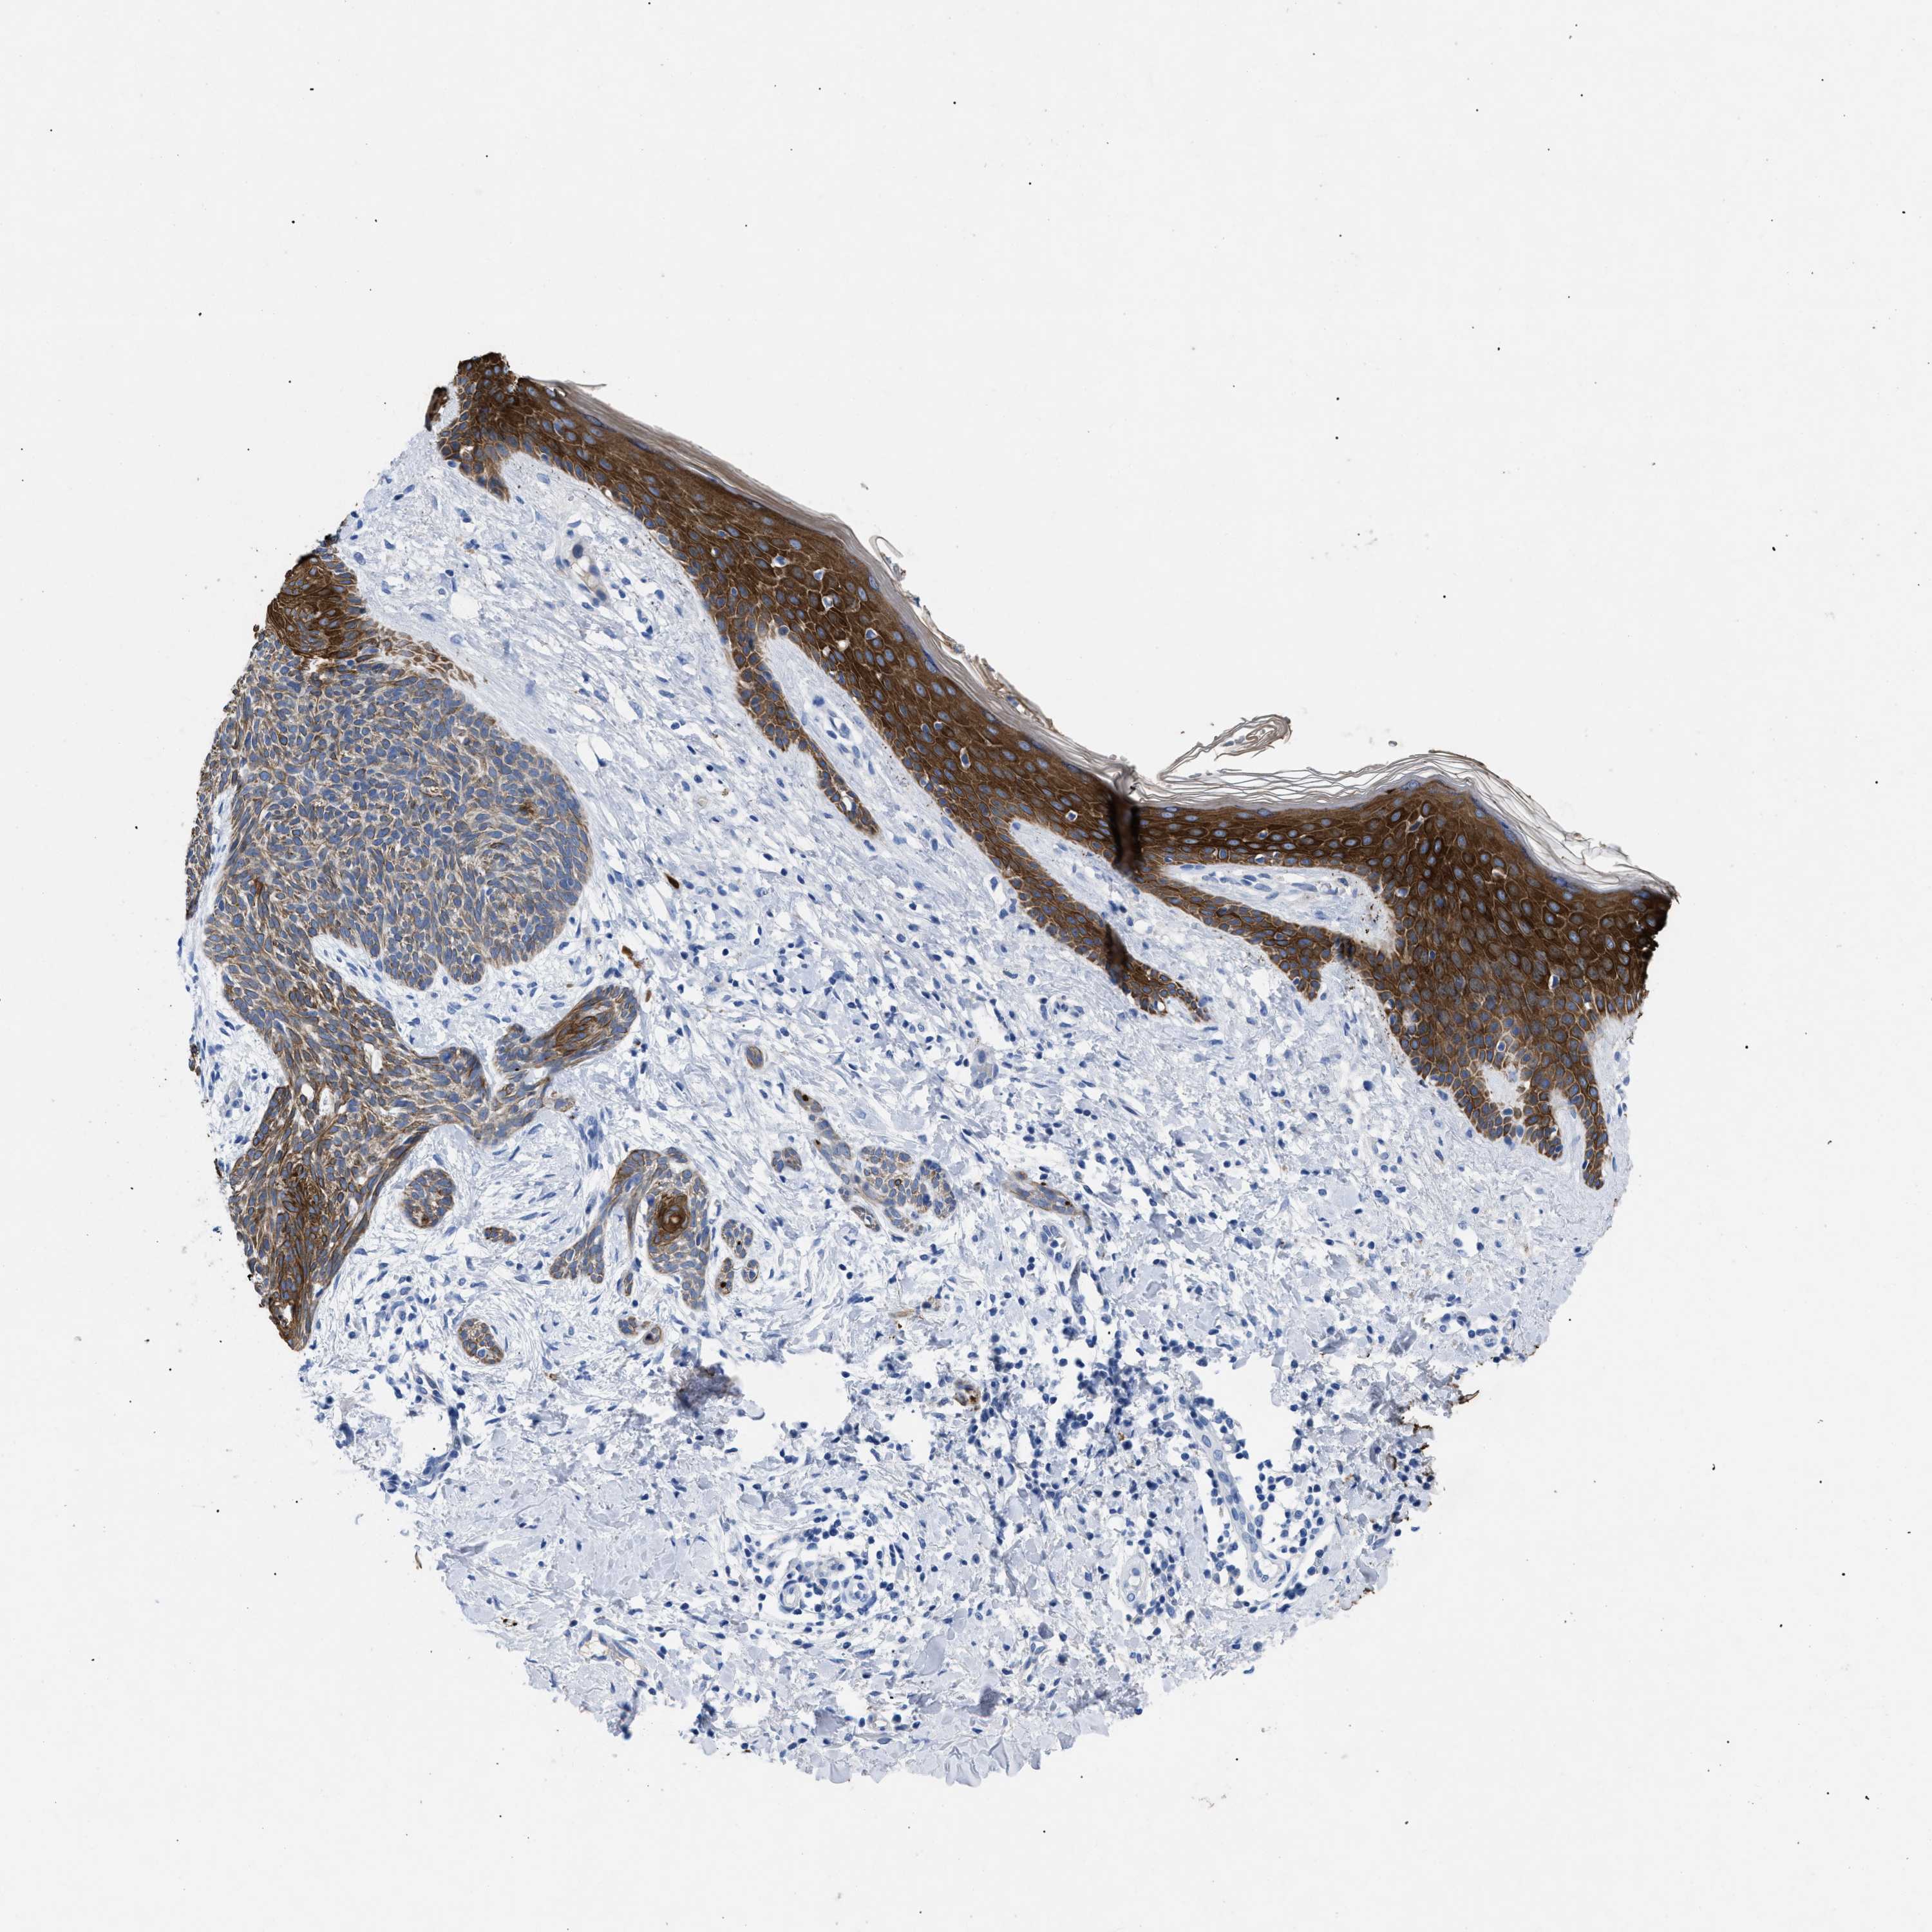

SKIN CANCER - Protein expressioni

A mouse-over function shows sample information and annotation data. Click on an image to view it in a full screen mode. Samples can be filtered based on level of antibody staining by selecting one or several of the following categories: high, medium, low and not detected. The assay and annotation is described here.

Each image is clickable and will lead to virtual microscopy that enables deeper exploration of all samples and also displays staining intensity scores, fraction scores and subcellular localization as well as patient and tissue information for each sample.

Antibody HPA019173

Staining

Medium

Intensity

Moderate

Quantity

75%-25%

Location

Cytoplasmic/membranous

Squamous cell carcinoma, NOS